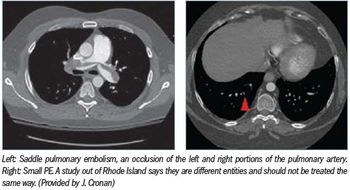

Nearly two years after a paper titled “Dots are not clots: the over-diagnosis and over-treatment of pulmonary embolism” was presented at the RSNA meeting, radiologists are still debating when to put patients on anticoagulation therapy.